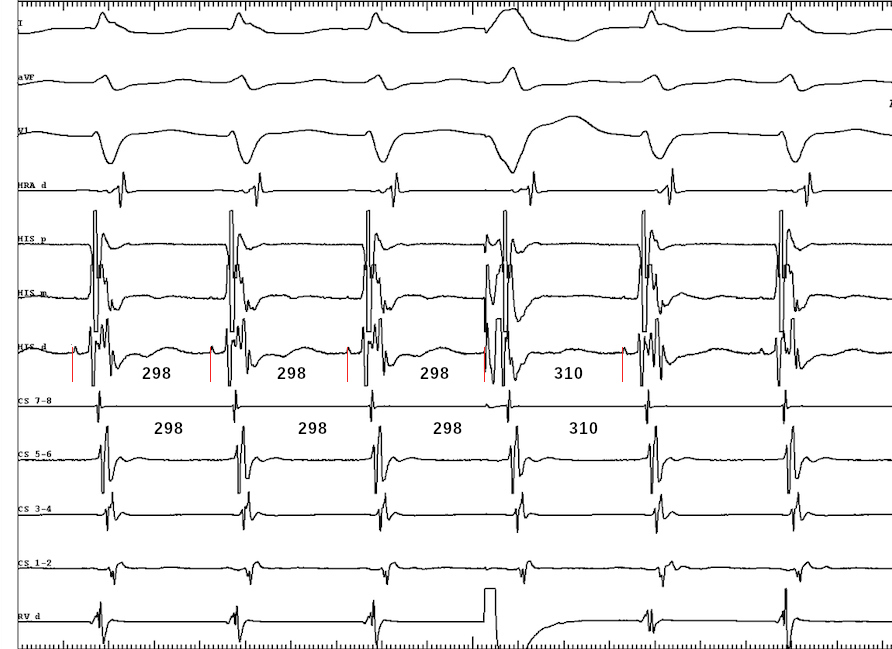

Case 2 - 42 F - Tachy induced with A extra. VA 126

tachy.jpg

PVC on time with His

pvc.jpg

VOP from base - cPPI-TCL 140 ms

vop_base.jpg

VOP from apex - cPPI-TCL 180 ms

vop.jpg

VA from base and apex

Diagnosis

• Atypical AVNRT

• Bystander concealed nodoventricular AP

• Successful ablation at RIE